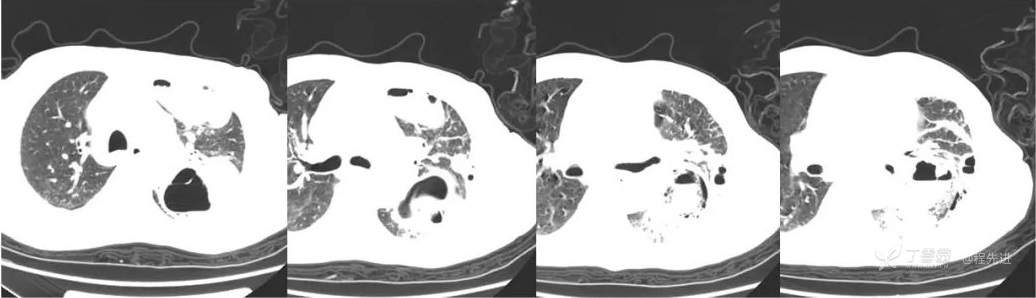

CT平扫

肺窗